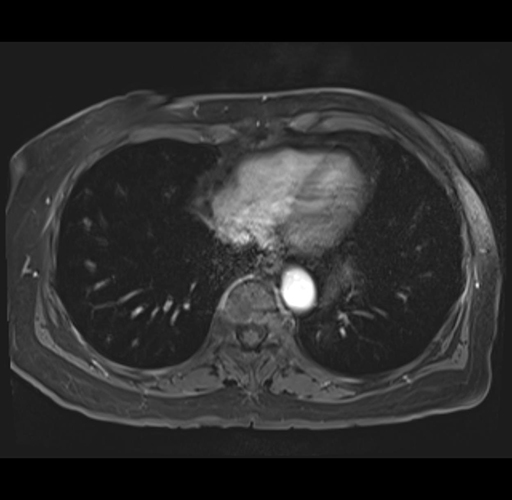

MRI T1